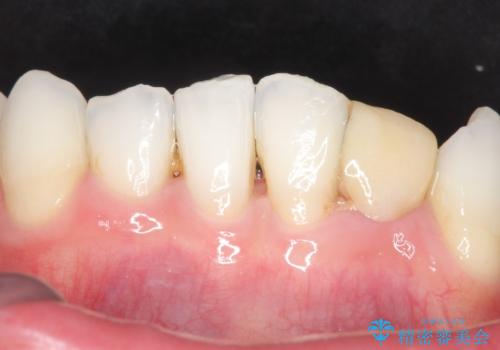

- 他院にて矯正治療を行ったが、左下の前歯の見た目が気になるのでセラミックで治したいといらっしゃった方の症例です。

左下123番のブリッジになるが、左下1番と3番の歯軸が合っておらず神経治療が必要になる可能性があるため部分矯正を提案したところ、希望されなかったため、そのままの歯軸でオールセラミッククラウンによる補綴を行いました。